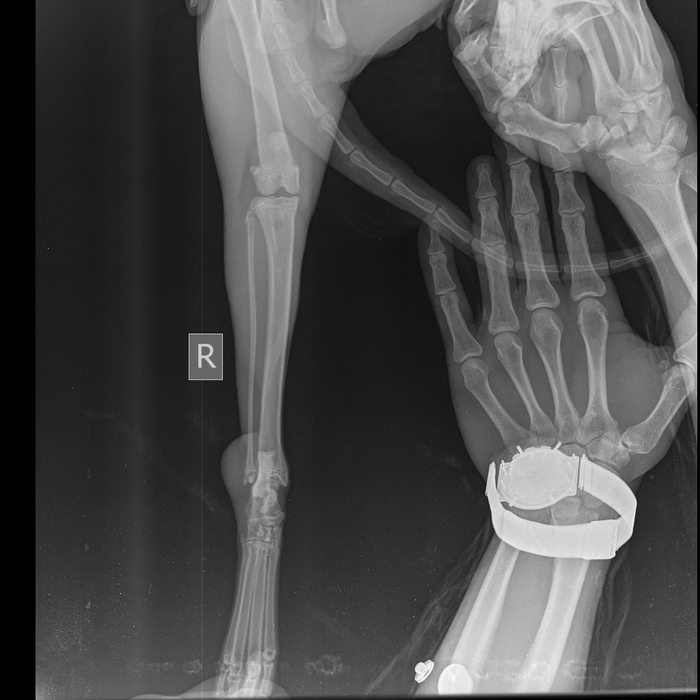

2 августа эта красота решила отметить праздник. Отодрала сетку с балконного окна и сиганула с 5 этажа без парашюта (скорее всего голуби радразнили). Дома никого не было. Судя по всему приземлилась на газон, доковыляла до околопод'ездной лавочки и дождалась меня. -1 кошачья жизнь, контузия правого легкого, ушиб двух правых лап, обошлось без переломов.